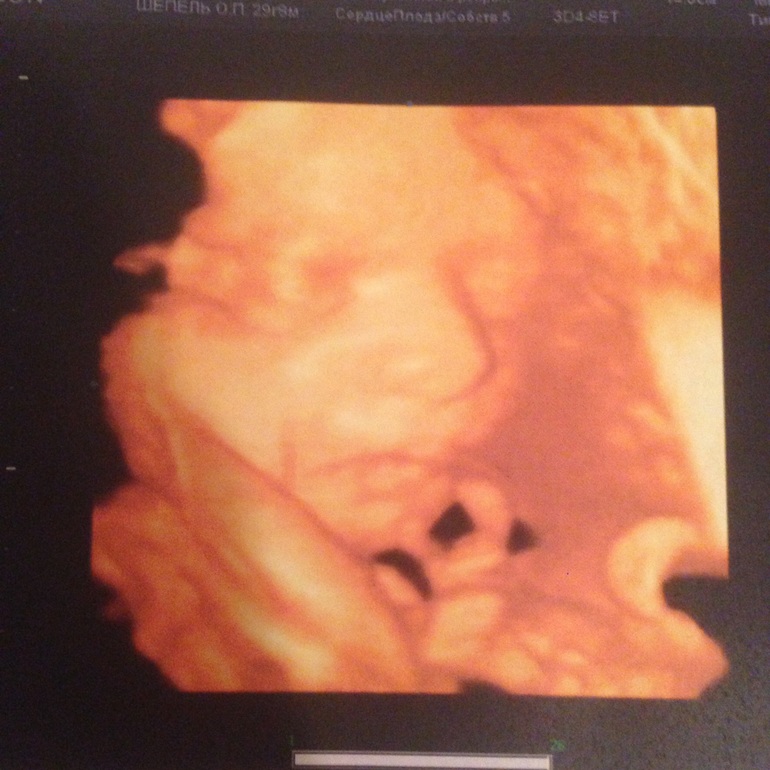

Результаты: УЗИ, КТГ, доплера, скринингаВчера были на узи. С первой минуты когда я легла врач сказала, ваша девочка отвернулась спинкой но это и так почувствовала, ибо выпекала она в одну сторону. 100% девочка четко показалась. Весит 1180, рост 38 см, все показатели соответствуют сроку, вот только животик немного худенький на 28 недель, но врач сказала что это не повод для беспокойства, так как мол мы с мужем маленькие и худенькие. Обвитая нет, лежит в головном. Шейка закрыта 38 мм небольшой загиб, сказала что такая шейка не требует контроля. Воды в норме, зрелость плаценты нулевая. Была в ЦИРе у Евстегнеевой, мы с мужем остались довольны. Ну и наше фото недовольной моськи

кроха не любит узи. Теперь пойдем только на скрининг.